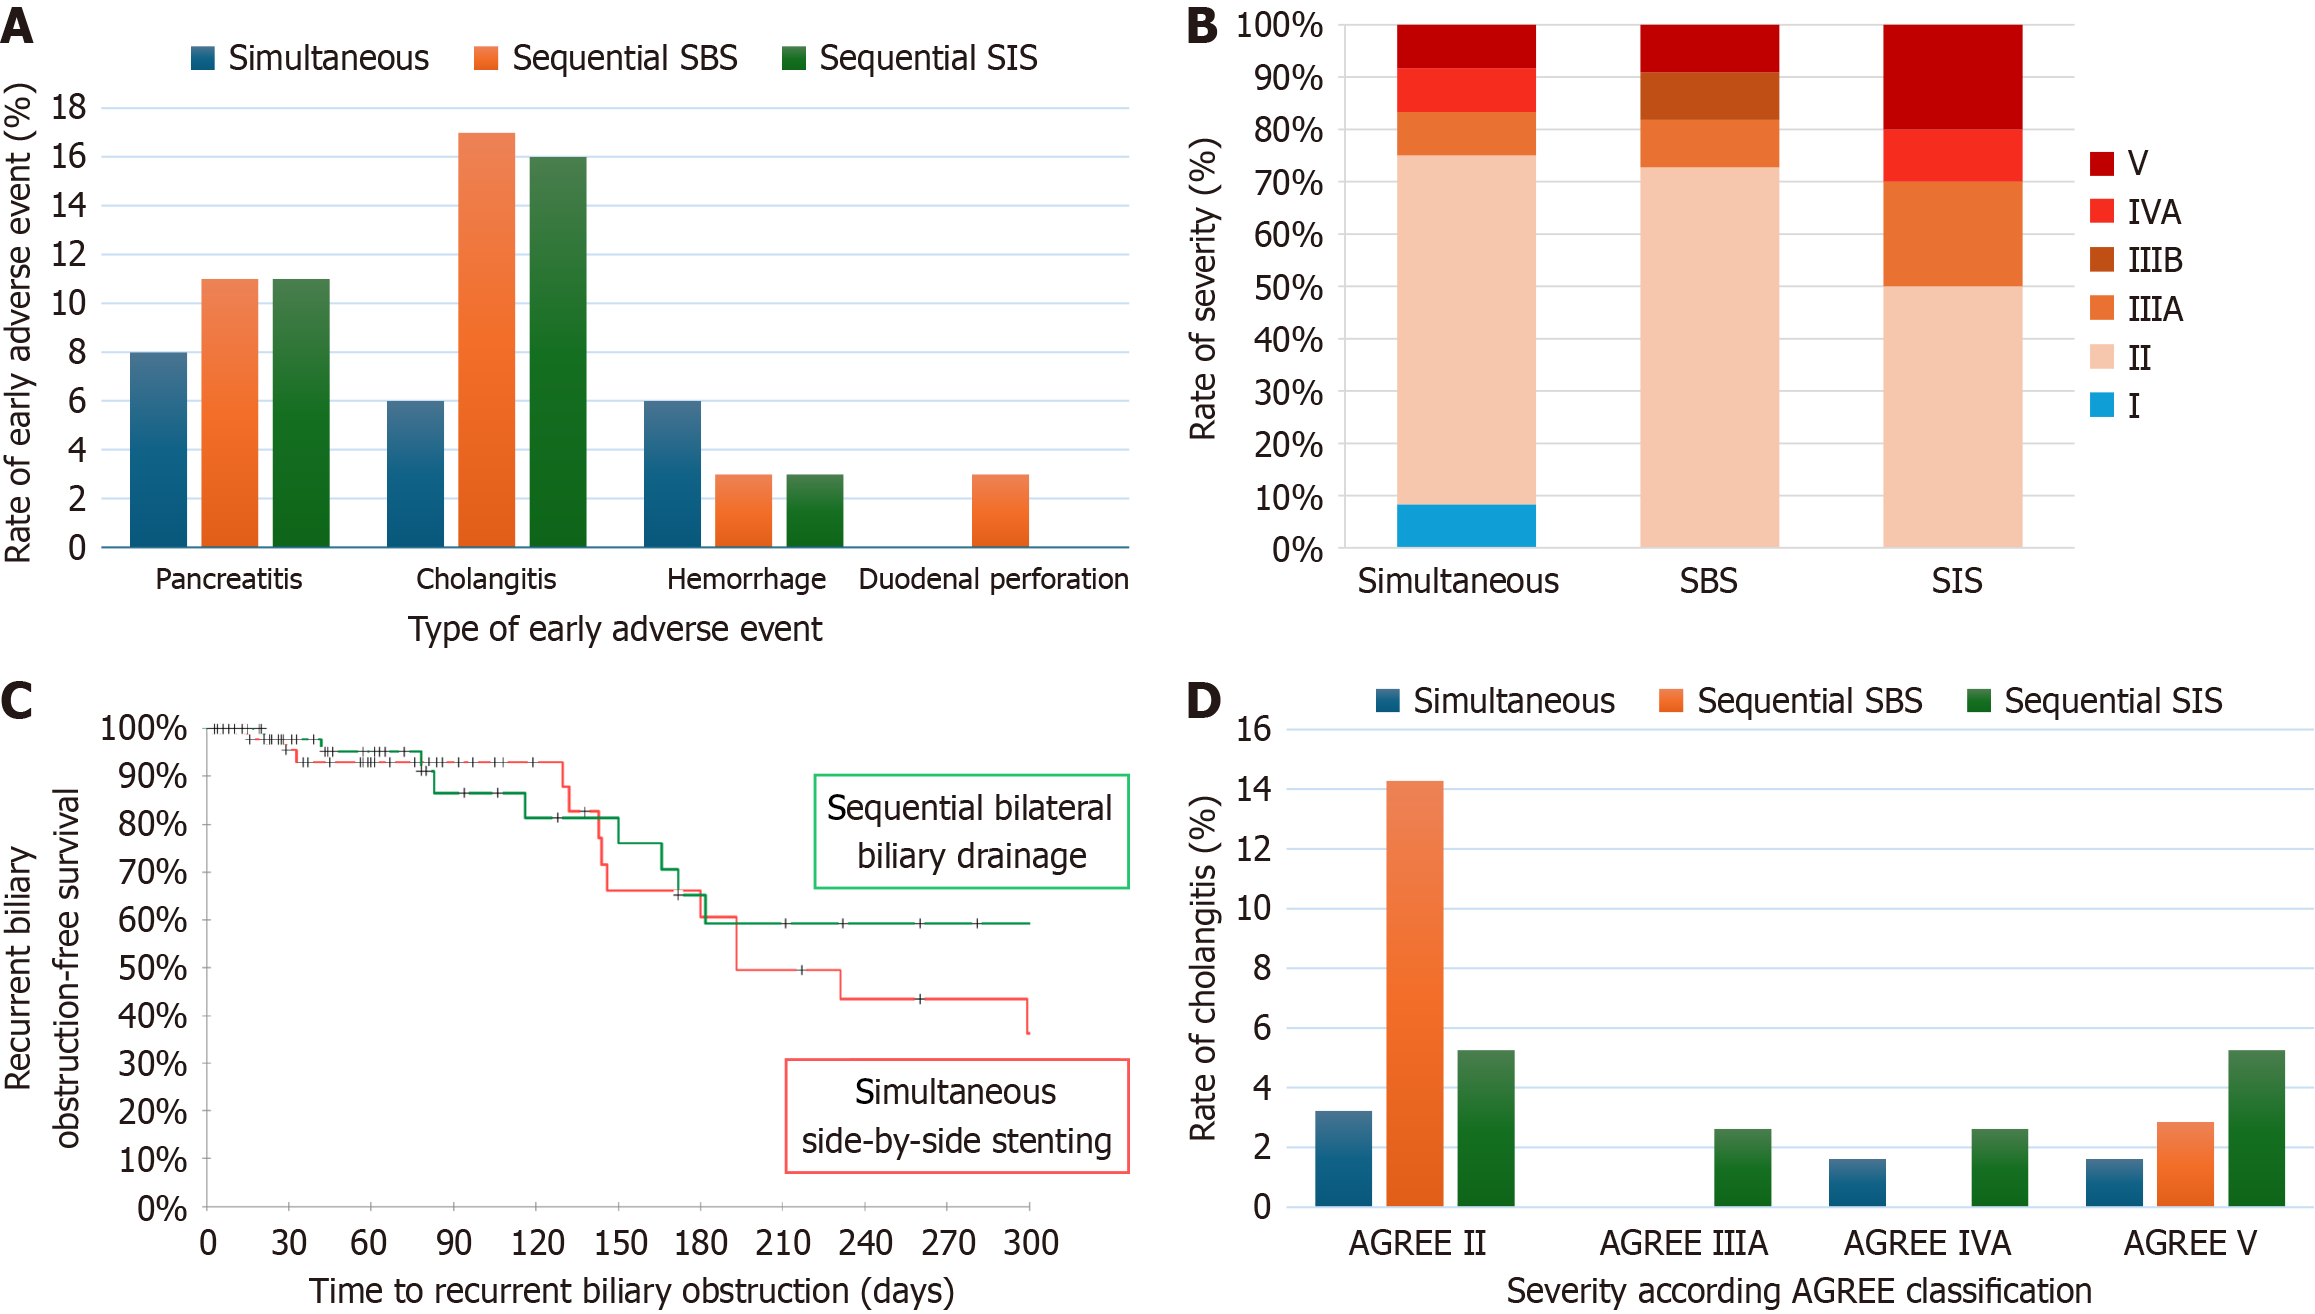

Figure 3 Flow diagram of the participants analyzed.

EUS-BD: Endoscopic ultrasound-guided biliary drainage; PTBD: Percutaneous transhepatic biliary drainage; ERCP: Endoscopic retrograde cholangiopancreatography.

Figure 4 Adverse event and recurrent biliary obstruction outcomes.

A: Rate of early adverse events among groups; B: Repartition of severity according the Adverse Event Gastrointestinal Endoscopy classification among patients who suffered from an adverse event; C: Kaplan-Meier curves compared recurrent biliary obstruction-free survival between simultaneous and sequential groups; D: Repartition of severity according to the Adverse Event Gastrointestinal Endoscopy classification among patients with cholangitis. AGREE: Adverse Event Gastrointestinal Endoscopy; SBS: Side by side; SIS: Stent in stent.